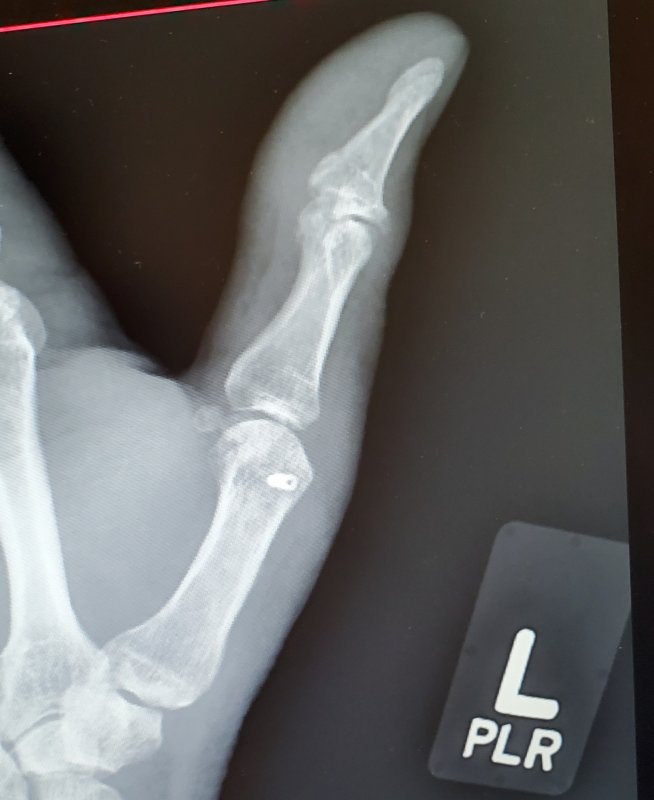

This was the opposite of skier's thumb. Riding home after my crash, couldn't use my thumb for the dropper. Had to use my palm.Ooof. Mine was classic skier's thumb caused by the grip when I went OTB on a step-up attempt. My thumb was so slack after it that it couldn't even resist slight pressure, just bent right back..